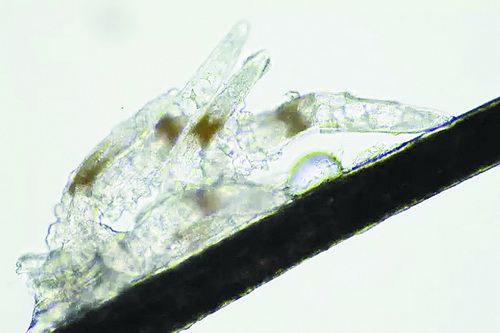

顯微鏡下長在睫毛中的螨蟲

冬天來了,氣溫降低,睫毛上的“隱形殺手”蠕形螨卻沒有要冬眠的意思。廈門大學(xué)附屬廈門眼科中心11月初開設(shè)蠕蟲性瞼緣炎門診以來,每天來查螨的市民都特別多,短短一個多月,已有近千人在顯微鏡下見到長期寄居在自己睫毛上,朝夕相處,卻素未謀面的蠕形螨。

蠕形螨怎么就跑進眼睛里了呢?原來,蠕形螨以吃角質(zhì)蛋白、油脂為生,而我們的睫毛和瞼板腺等地方油脂分泌旺盛,正是螨蟲寄居的理想場所。蠕形螨有兩種,一種是寄生在睫毛、眉毛毛囊里的毛囊蠕形螨,一種是寄生在皮脂腺和瞼板腺內(nèi)的皮脂蠕形螨,它們在眼睛里吸食油脂、吞噬上皮細胞、產(chǎn)卵、排泄,會引發(fā)一系列不良反應(yīng)。